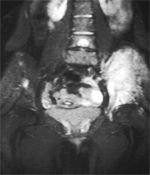

MRI showing Ewing's sarcoma of the left hip.